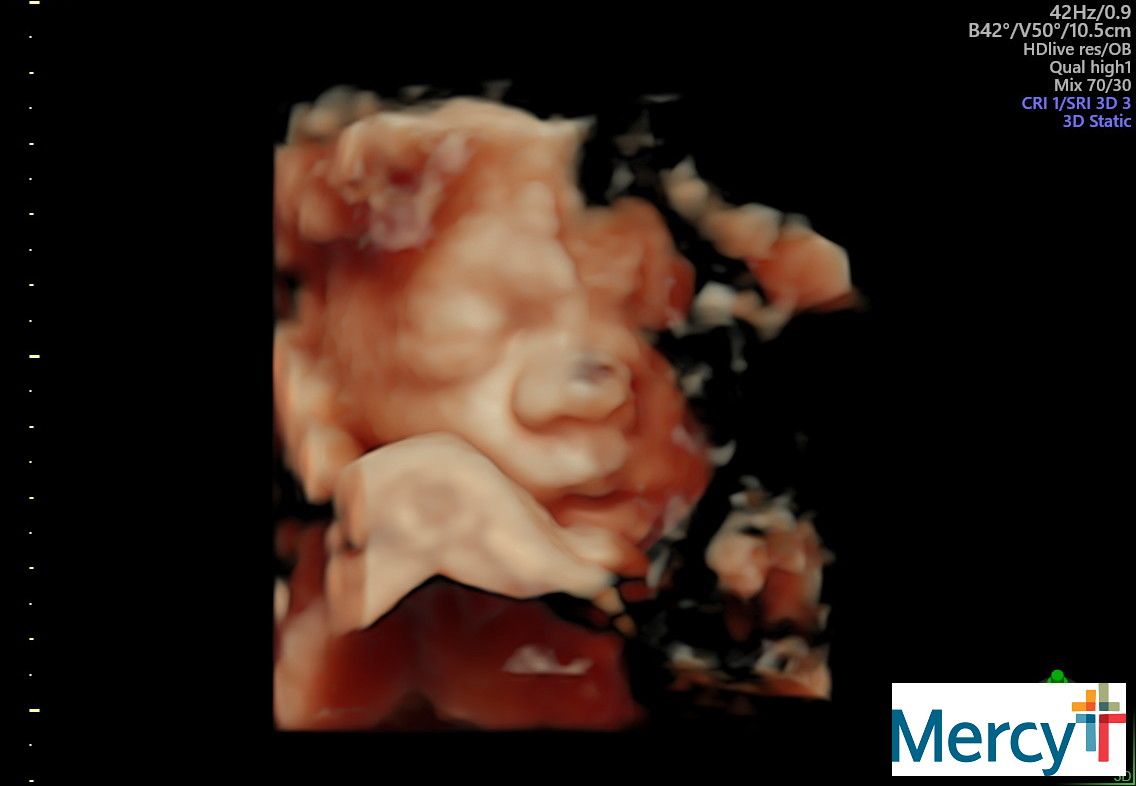

The belly is in full swing! Look at this face!